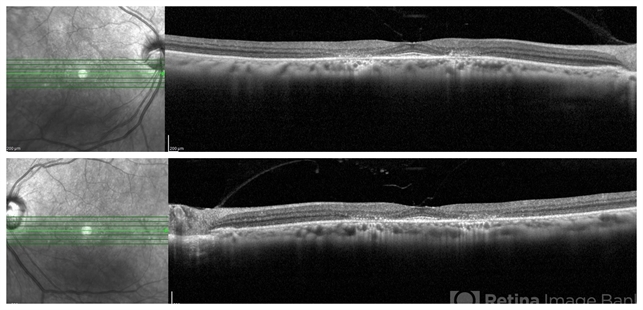

- plaquenil toxicity, hydroxychloroquine toxicity, bull's eye maculopathy

- Optical coherence tomography system

- SD- OCT of the same patient with hydroxychloroquine (Plaquenil) toxicity, demonstrating classic "Flying Saucer" pattern secondary to parafoveal RPE atrophy, and outer retinal layer disruption including EZ loss, and outer nuclear layer loss.